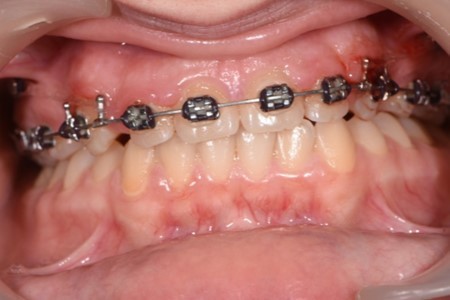

Figure 4.Treatment start - Orthodontic appliance on the upper arch, Roth 022" prescription.

Treatment started with orthodontic appliances on the upper arch, Roth 022" prescription. In order to achieve a better retraction of the upper teeth, first bicuspids were extracted. Retraction of the upper incisors with elastics chains placed from crimpable hooks to orthodontic implants.